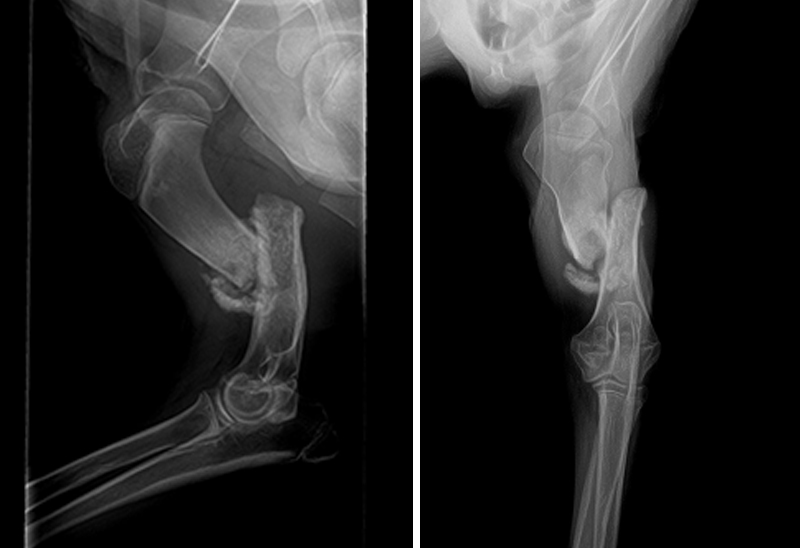

When our medical team carried him in, his front leg was swollen and painful. X-rays revealed a bad break with the bone jutting into his upper leg. He is now on pain medications and resting comfortably, but his leg is beyond repair and needs to be amputated.